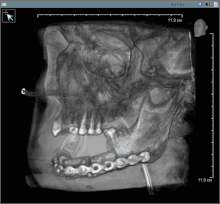

Surgery

In most centres, removal of squamous cell carcinoma from the oral cavity and neck is achieved primarily through surgery. This also allows a detailed examination of the tissue for histopathologic characteristics, such as depth, and spread to lymph nodes that might require radiation or chemotherapy. For small lesions (T1–2), access to the oral cavity is through the mouth. When the lesion is larger, involves the bone of the maxilla or mandible, or access is limited due to mouth opening, the upper or lower lip is split, and the cheek pulled back to give greater access to the mouth.[33] When the tumor involves the jaw bone, or when surgery or radiation will cause severe limited mouth opening, part of the bone is also removed with the tumor.